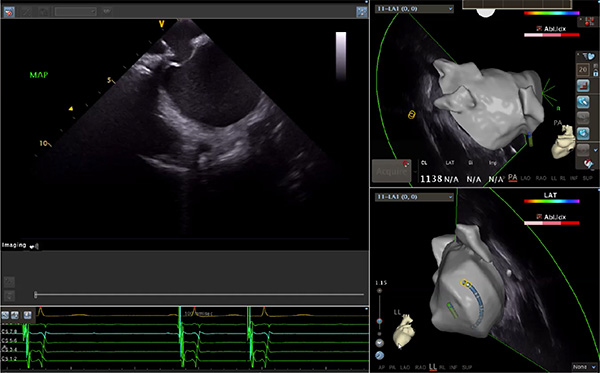

超聲心動(dòng)圖技術(shù)包括常規(guī)經(jīng)胸超聲(TTE)、經(jīng)食管超聲(TEE)、心腔內(nèi)超聲(ICE)、超聲聲學(xué)造影(MCE)、三維超聲心動(dòng)圖等,ICE是一種新興技術(shù)——將微型的換能器安裝在心導(dǎo)管的尖端,經(jīng)由外周血管輸送至心腔內(nèi)部,換能器發(fā)射聲波,對(duì)心臟及其鄰近組織進(jìn)行實(shí)時(shí)高質(zhì)量成像和(或)血流動(dòng)力學(xué)測(cè)定的超聲成像技術(shù)?;诓煌募夹g(shù)原理,心腔內(nèi)超聲導(dǎo)管被分為兩類:機(jī)械旋轉(zhuǎn)式超聲導(dǎo)管和相控陣超聲導(dǎo)管。目前,臨床上主要應(yīng)用的是相控陣超聲導(dǎo)管,ICE成像通過(guò)術(shù)者旋轉(zhuǎn)導(dǎo)管及操縱導(dǎo)管手柄上的兩個(gè)旋鈕來(lái)完成。

ICE門(mén)檻高、集成了超聲和圖像處理最前端的技術(shù),是當(dāng)前內(nèi)窺超聲方向最挑戰(zhàn)的領(lǐng)域。不同于傳統(tǒng)接觸式三維重建方法會(huì)產(chǎn)生假腔,影響術(shù)者對(duì)靶點(diǎn)或結(jié)構(gòu)的判斷,心腔內(nèi)超聲(ICE)可直接顯示心臟結(jié)構(gòu),有助于理解心臟內(nèi)各部位之間的解剖關(guān)系,不僅具有實(shí)時(shí)成像、并發(fā)癥監(jiān)測(cè)以及良好的耐受性,同時(shí)以股靜脈入路,無(wú)需全麻或深度鎮(zhèn)靜,日益成為心臟介入手術(shù)中重要輔助工具,被譽(yù)為心臟介入醫(yī)生的“黃金眼”。心腔內(nèi)超聲可用于多種心臟介入手術(shù),潛在患者群體龐大,動(dòng)脈網(wǎng)測(cè)算我國(guó)心腔內(nèi)超聲導(dǎo)管市場(chǎng)空間或?qū)⒊?00億元,具有廣闊前景。

隨著心腔內(nèi)超聲的應(yīng)用更廣,性能也在逐漸優(yōu)化,已從二維成像轉(zhuǎn)變?yōu)?strong>三維成像,極大增強(qiáng)了引導(dǎo)及可視化能力。二維心腔內(nèi)超聲支持雙平面或三平面成像,可顯示兩個(gè)或三個(gè)不同的平面視圖,但醫(yī)生需將這些圖像在腦海中重新構(gòu)建為三維解剖結(jié)構(gòu)。三維心腔內(nèi)超聲則可直接呈現(xiàn)三維解剖結(jié)構(gòu)圖,便于醫(yī)生更輕松地開(kāi)展手術(shù)。按照產(chǎn)品發(fā)展方向,預(yù)計(jì)心腔內(nèi)超聲還將向更清晰、精準(zhǔn)、多功能等方向發(fā)展。